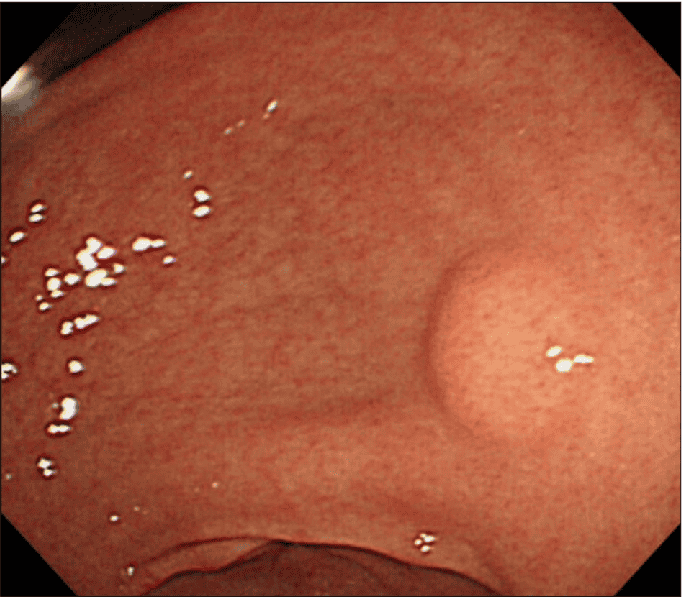

۵. لیپوم (Lipoma)

لیپومها تومورهای خوشخیم نادری هستند که از سلولهای چربی در دیواره معده ایجاد میشوند. این تومورها نیز زیرمخاطی بوده و پتانسیل سرطانی شدن آنها تقریباً صفر است.

-درمان لیپوم:

-عدم نیاز به درمان: از آنجا که لیپومها همیشه خوشخیم و معمولاً بدون علامت هستند، تقریباً هرگز نیاز به درمان ندارند. پزشک صرفاً وجود آن را ثبت کرده و تحت نظر میگیرد.

-برداشتن در موارد نادر: تنها در صورتی که لیپوم به اندازه بسیار بزرگی برسد و باعث ایجاد انسداد یا خونریزی شود (که بسیار نادر است)، برداشتن آن از طریق آندوسکوپی یا جراحی در نظر گرفته میشود.